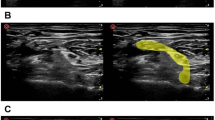

To develop gold standard atlases for BP contouring, 12 cadavers (age and gender randomized) were used. The cadavers were embalmed according to Thiel because of their optimal image quality and movement capacities [22, 23]. The latter allowed for the required standardization of the scan position. Magnetic resonance imaging (MRI) of the head-and-neck region was performed to generate high-quality BP delineations that were anatomically validated by dissection. These anatomically validated, MRI-based, BP delineations were then rigidly fused to the corresponding CT to obtain BP gold standard delineations that were applicable to the radiation therapy planning system. A detailed description was provided by Van de Velde et al. [24]. This study was approved by the ethics committee of University Hospital Ghent (reference number: B67020142069), and was in compliance with the Helsinki Declaration.